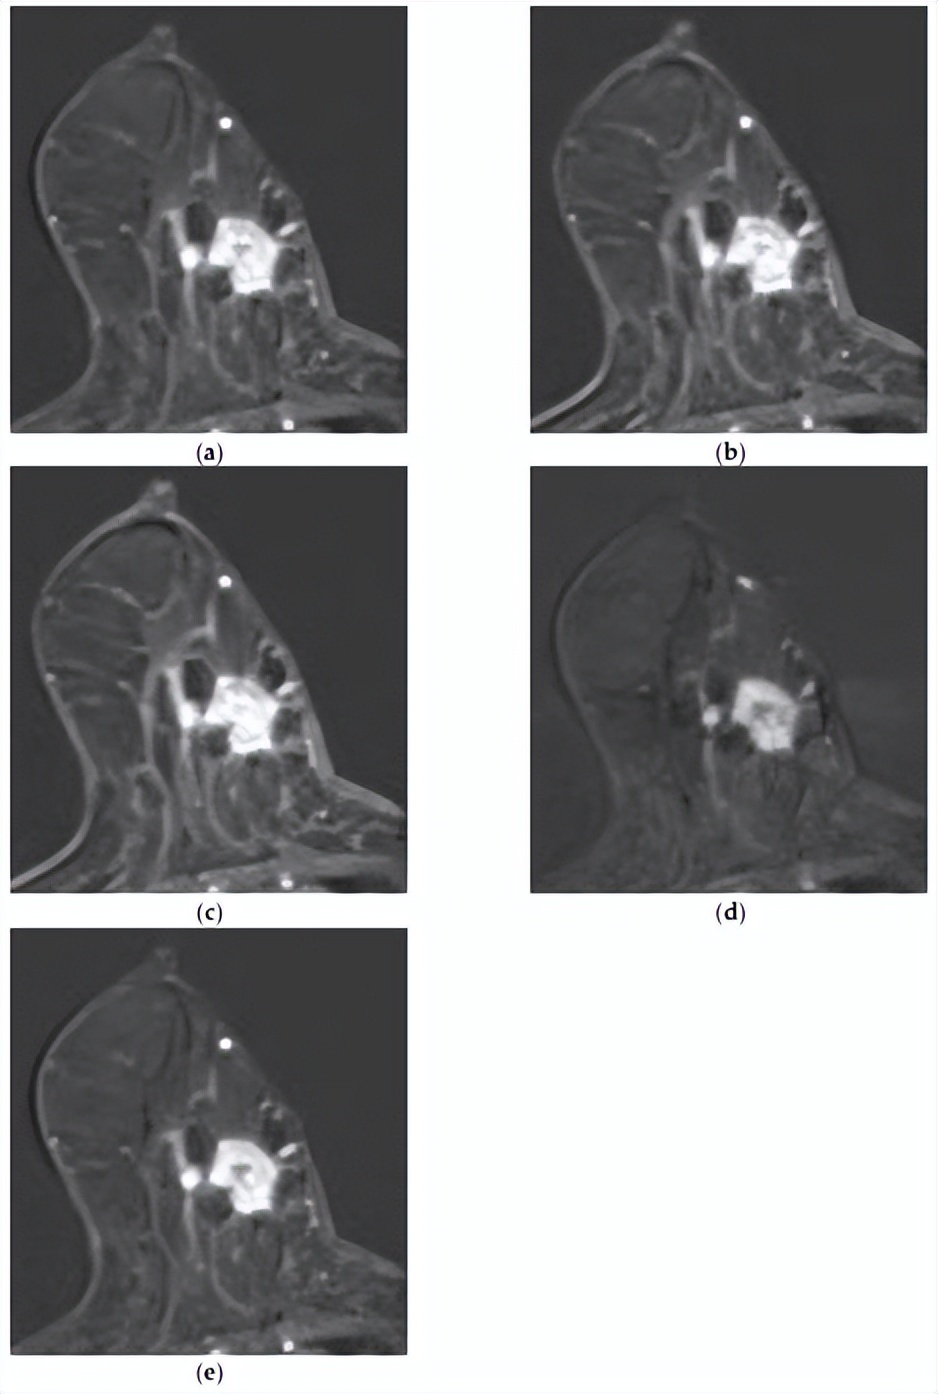

[组合模型正确预测了复发,而MRI模型则没有。一名73岁的女性,乳房几乎完全脂肪化,BPE极小。注射造影剂后(a)1分钟、(b)2分钟、(c)3分钟、(d)4分钟和(e)5分钟的轴向增强T1加权MR图像显示,右下内象限有一个1.4×1.7厘米的不规则形状、边缘不规则肿块,内部增强不均匀。病灶表现出快速的初始增强,随后呈现平台期动力学曲线模式。未发现腋窝淋巴结转移。MRI深度学习模型无法预测该复发病例,但整合临床病理学和MRI特征的组合模型可以正确预测。]

△HER2低表达乳腺癌复发的代表性病例